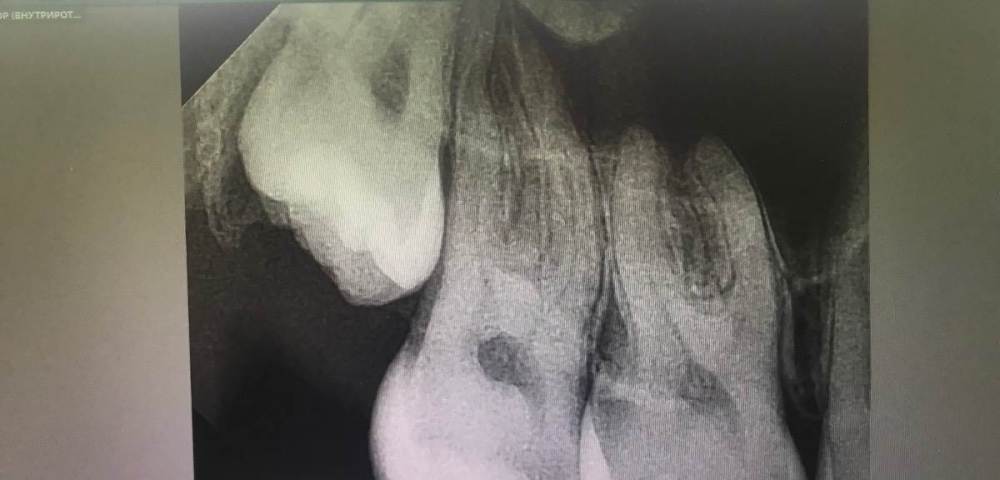

cryptiik Опубликовано 16 февраля, 2023 Поделиться Опубликовано 16 февраля, 2023 Расшифруйте, пожалуйста, снимки 16 и 17 зубов. Ссылка на комментарий

annda Опубликовано 16 февраля, 2023 Поделиться Опубликовано 16 февраля, 2023 Для точной оценки глубины и расположения полостей нужны прикусные снимки.А для диагноза -жалобы и объективные данные,а не вот эта абстракция. 1 Ссылка на комментарий